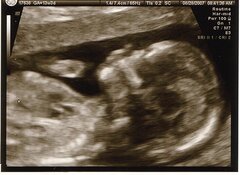

En août et septembre prochains, le Comité des droits des personnes handicapées (CRPD) des Nations Unies examinera la situation des personnes handicapées et de leurs droits en Belgique. Parmi les questions qui pourraient être soulevées, figurent les implications du dépistage systématique de la trisomie 21 au stade de la grossesse.

Sur le plan bioéthique, il reste à savoir si le CRPD se penchera sur les implications sociales et éthiques du dépistage généralisé des trisomies au stade prénatal en Belgique, par le biais du NIP-test. Ce test sanguin, non invasif, est systématiquement proposé aux femmes enceintes, et par ailleurs entièrement remboursé par l’État belge. Aucune campagne officielle n’est menée pour encourager les femmes et les couples à garder l’enfant, ou, à l’inverse, à se tourner vers l’avortement en cas de détection d’une trisomie (en particulier pour la trisomie 21, la plus fréquente). Si les soignants sont censés laisser le choix aux couples confrontés à cette annonce, plus de 95% des grossesses sont néanmoins avortées en cas de diagnostic de la trisomie 21 en Belgique (voy. IEB 25/02/2021).